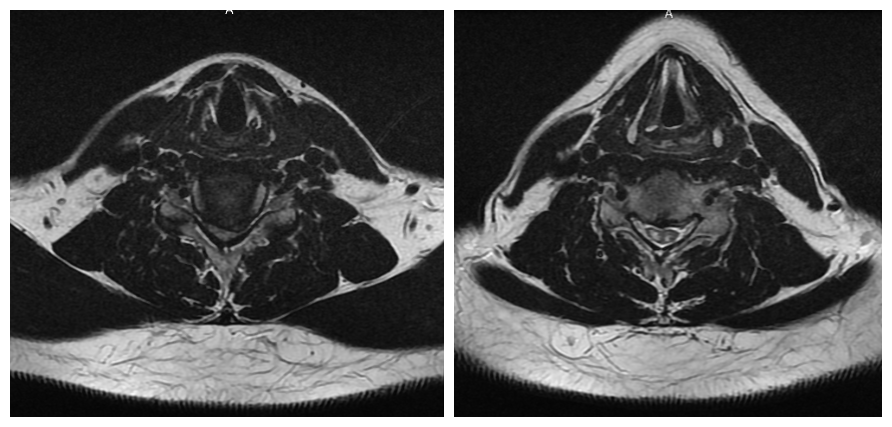

(颈椎MRI横断位:颈5-6椎间盘中央偏左突出,脊髓横截面积减少大于1/2,脊髓变性,增强的信号像是两只眼睛,被称为“眼镜蛇征”)